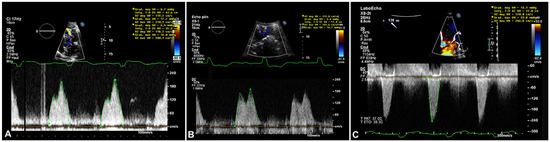

Figure 5.

A. Transthoracic echocardiogram (TTE), continuous Doppler transmitral mean gradient (6 mm Hg at 80 bpm) on initial presentation in 2016 B. TTE, continuous Doppler transmitral mean gradient (6–7 mm Hg at 65 bpm) 4years later in 2020. C. Transoesophageal echocardiogram, continuous Doppler transmitral mean gradient (6–13 mm Hg at 85 bpm) in 2020.

Table 1). The patient was admitted for oxygen supplementation and intravenous diuretics with rapid recovery ensuing in a few days. A TTE documented normal heart function but an increase in the size of the cardiac mass ( 46 mm × 31 mm compared with 36 mm × 27 mm 4 years before), the mean gradient across the mitral valve was unchanged at 6–7 mm Hg at a heart rate of 65 bpm (

Figure 3A). Remarkably, there was an increase in the mean diastolic mitral gradient from 6 mm Hg at the time of the TTE to 13 mm Hg on TOE, probably due to a higher heart rate of 85 bpm (

Figure 5). A CT scan showed an increased size of the mass (